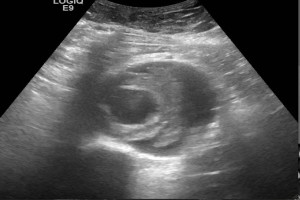

Diplomados en Ultrasonografía